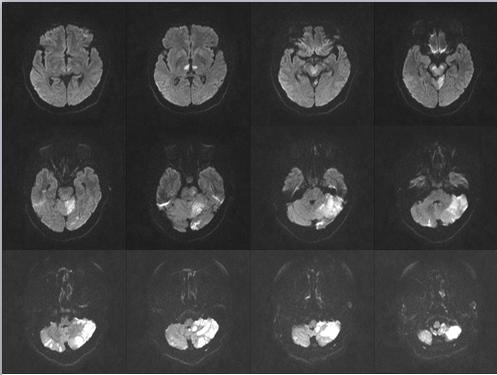

按照“先诊疗,后付费”救治原则,脑卒中救治医生全程陪护,第一时间完成头颈部CT血管成像,可以明确闭塞的基底动脉完全再通,随即收治入神经内一科重症病房,通过后续治疗,患者病情好转,生活恢复正常。

患者入院后头颅磁共振弥散成像